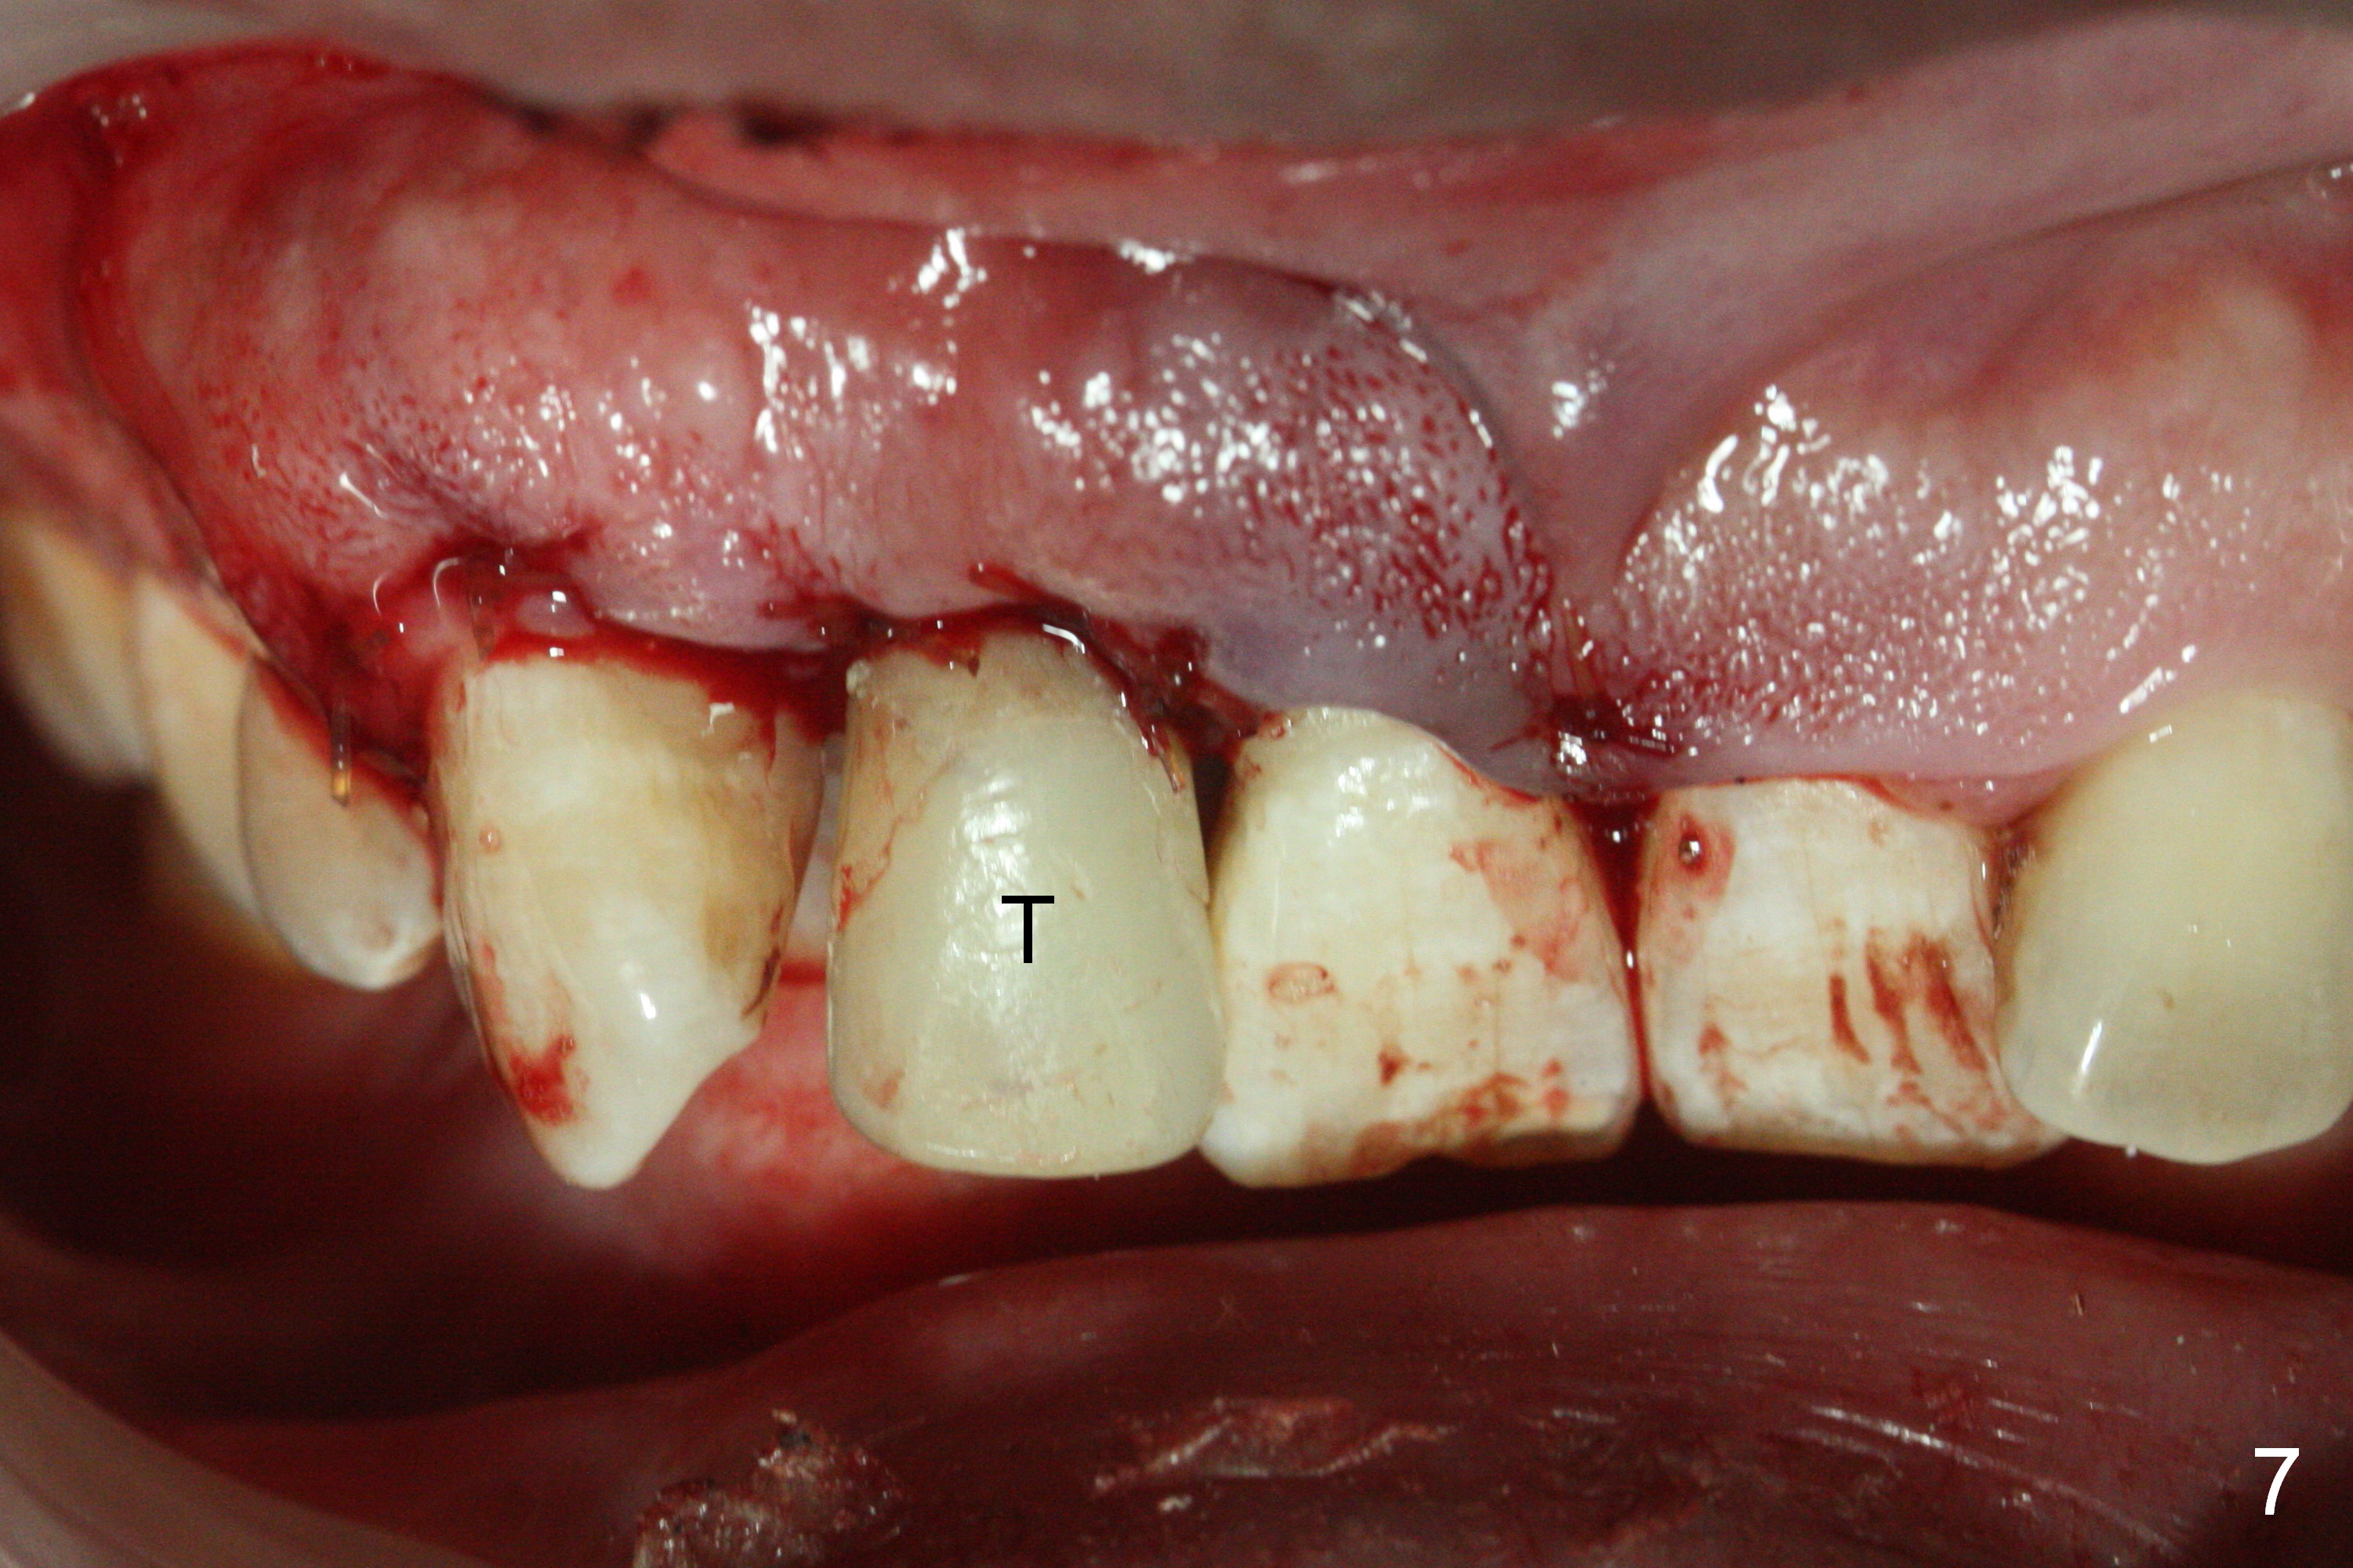

When the flaps are raised, the buccal plate is found to be perforated (Fig.2 *); osteotomy is being established in the narrow palatal wall (<). When a 3x17 mm (tissue-level) 15 ° 1-piece implant is placed (Fig.3,5 P), the incisal end of the implant is between the incisal edge of the central incisors and that of the tooth #10 (Fig.6) so that the temporary crown (Fig.7 T) is slightly buccal with sufficient palatal clearance with the opposing dentition.

Sixteen days postop, the patient is doing fine, although the labial fistula has not disappeared (Fig.8 <). The detached distolabial papilla is healing (Fig.9 *) with mild bone graft exposure (^). The lacerated distopalatal papilla is also healing (Fig.10 *). These complications are related to flap surgery. The apical portion of the socket appears to have reduced 4 months postop (Fig.14). When the definitive restoration is delivered 5 months postop, there is gingival recession, including the distal of #8 (Fig.11 arrows, which is expected to improve over time) due to flap surgery. The labial plate collapse is minimal (Fig.12 *), while the palatal laceration (Fig.10) has healed (Fig.13). When the patient returns 1.5 years post cementation, there is increased bone density next to the coronal portion of the implant, equivalent to the bone graft (Fig.15 *). The fistula is absent (Fig.16). The crestal bone loss remains 2.5 years post cementation (Fig.17 *), although there is no sign of periimplantitis (magnification). Oral hygiene is poor. There is no change in the soft (gingival recession; data not shown) or hard tissues 3 years 8 months post cementation (Fig.18).